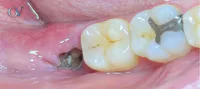

Un paciente de 35 años con antecedentes de diabetes tipo II mal controlada se presenta con dolor en su mandíbula y fiebre. Tiene una úlcera en la encía que no ha cicatrizado en varios meses. producto de una extraccion Las imágenes muestran los siguientes signos.

es una alveolitis

maxilar inferior de aproximadamente 3 cm se evidencia pequeños secuestros óseos y destrucción amplia esta imagen es compatible con una osteomilitis

imagen radiolucida en el maxilar inferior de aproximadamente 3 cm se evidencia pequeños secuestros óseos y destrucción amplia esta imagen es compatible con una osteomilitis